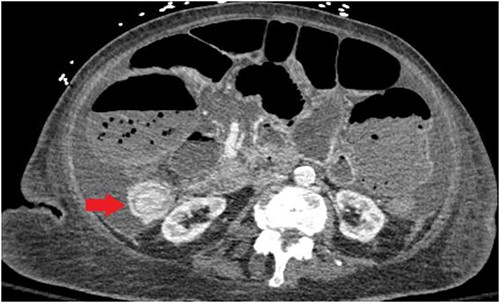

Unfortunately, the patient was diagnosed in April 2021 with complaints of nausea and vomiting and subsequently was found to have an intestine lesion causing intussusception and obstruction, which was perforated, resulting in an emergent surgical exploration and a palliative ileostomy (Fig. 3).

CT abdomen/pelvis displaying intussusception of terminal ileum.

In the case described above, there was a diagnosis of LCIS of the right breast in 2005. In 2019, the patient was found to have invasive lobular breast cancer T3N1M1, ER positive, PR positive, HER2neu negative. The patient might have a harbinger of carcinoma at the time of LCIS diagnosis that might have been missed, or there was a subsequent development of carcinoma in a later stage, which is very difficult to ascertain as the patient lost to the regular follow-up (Fig. 4).